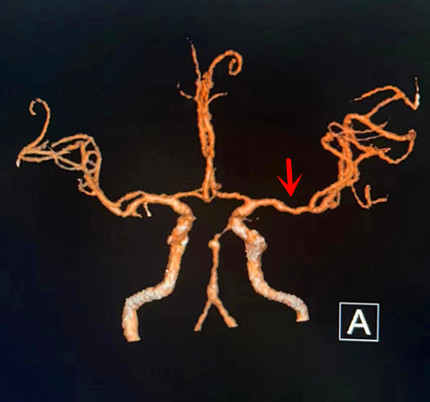

卒中中心醫護人(rén)員(yuán)向醫務科(kē)報告情況後,對患者予以靜(jìng)脈溶栓治療。從(cóng)患者進入我院到開始靜(jìng)脈溶栓,DNT時間(指從(cóng)患者發病入院到使用溶栓藥治療的這一時間)爲40分(fēn)鍾。當班醫生(shēng)立即爲患者進行核磁共振血管評估,結果顯示:責任血管左側大(dà)腦中動脈嚴重狹窄,遠(yuǎn)端分(fēn)支減少。

1小時後,患者意識恢複清醒,且肢體(tǐ)能夠在床面上活動。經過進一步治療,患者的語言障礙和肢體(tǐ)無力症狀得(de)到明顯改善, CTA評估提示血管再通。